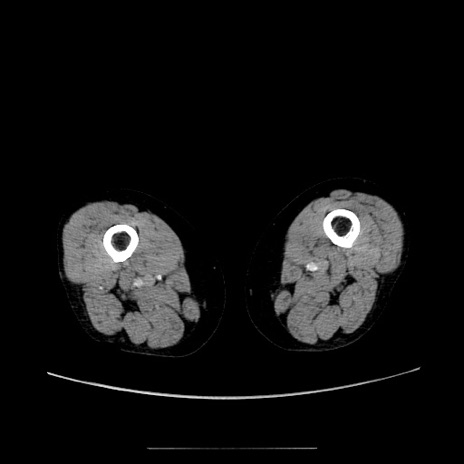

冠状断像

【症例】70歳代女性

【主訴】お腹が張る

【現病歴】1週間くらい前から腹部膨満の自覚あり。昨日夜から増悪したため、本日救急外来受診。

【身体所見】意識清明、BT 36.5℃、BP 165/106mmHg、HR 80bpm、SpO2 98%、腹部:膨満、軟、自発痛・圧痛なし、触診にて不快感あり、腸蠕動音:減弱

【データ】WBC 12600、CRP 1.04